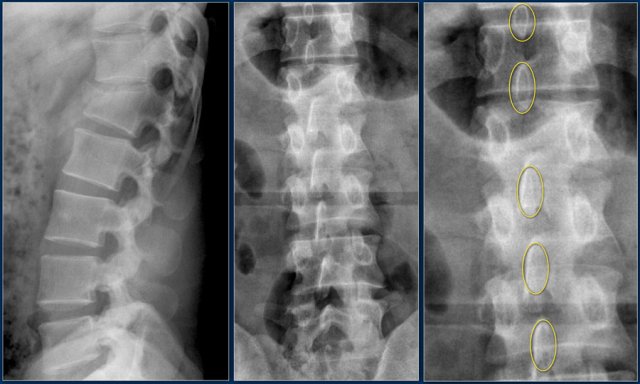

Widening of the interpedicular distance

Widening of the interpedicular distance, often a result of the sagittal fracture, is seen in 80% of burst fractures.

The lateral view shows the typical features of a burst fracture.

On the AP-view notice the subtle widening of the interpedicular distance compared to the levels above and below.